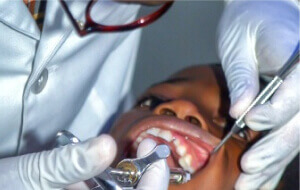

Comprehensive Dental Exams

Embark on a journey to optimal oral health with our Comprehensive Dental Exams. At Dr. Smith’s Dental Care, our meticulous approach ensures a thorough assessment of your dental well-being. Through detailed examinations, we delve into the intricacies of your oral health, detecting potential issues before they escalate. Our skilled team, led by Dr. Smith, combines advanced diagnostics with a commitment to personalized care. From assessing gum health to identifying potential decay, our comprehensive exams pave the way for proactive and preventive dental solutions.